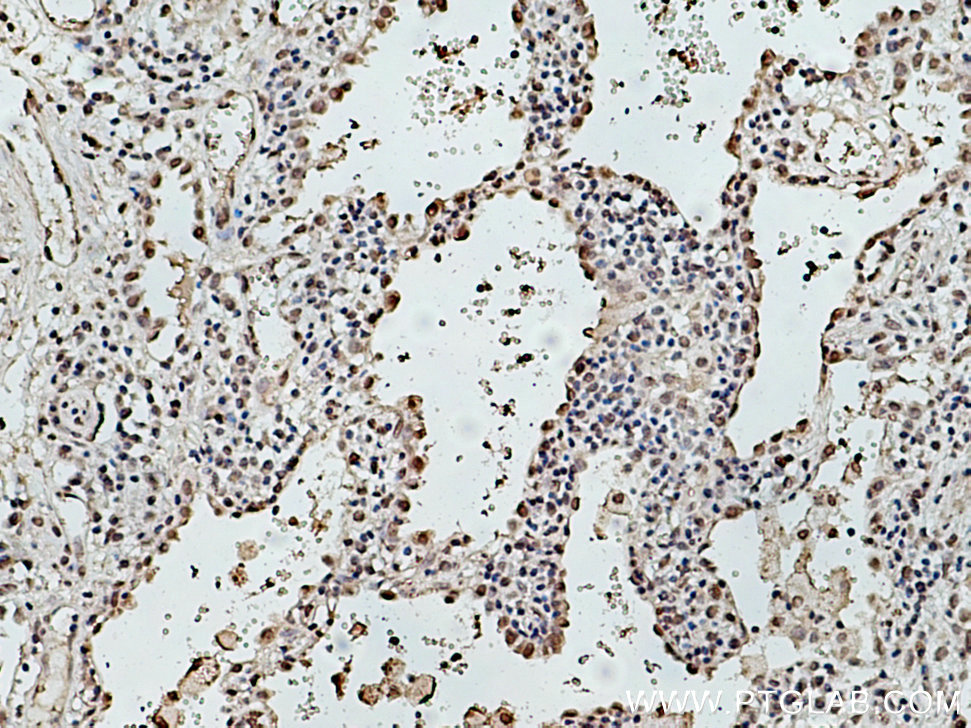

| Positive IHC detected in | human lung cancer tissue Note: suggested antigen retrieval with TE buffer pH 9.0; (*) Alternatively, antigen retrieval may be performed with citrate buffer pH 6.0 |

| Immunohistochemistry (IHC) | IHC : 1:50-1:500 |